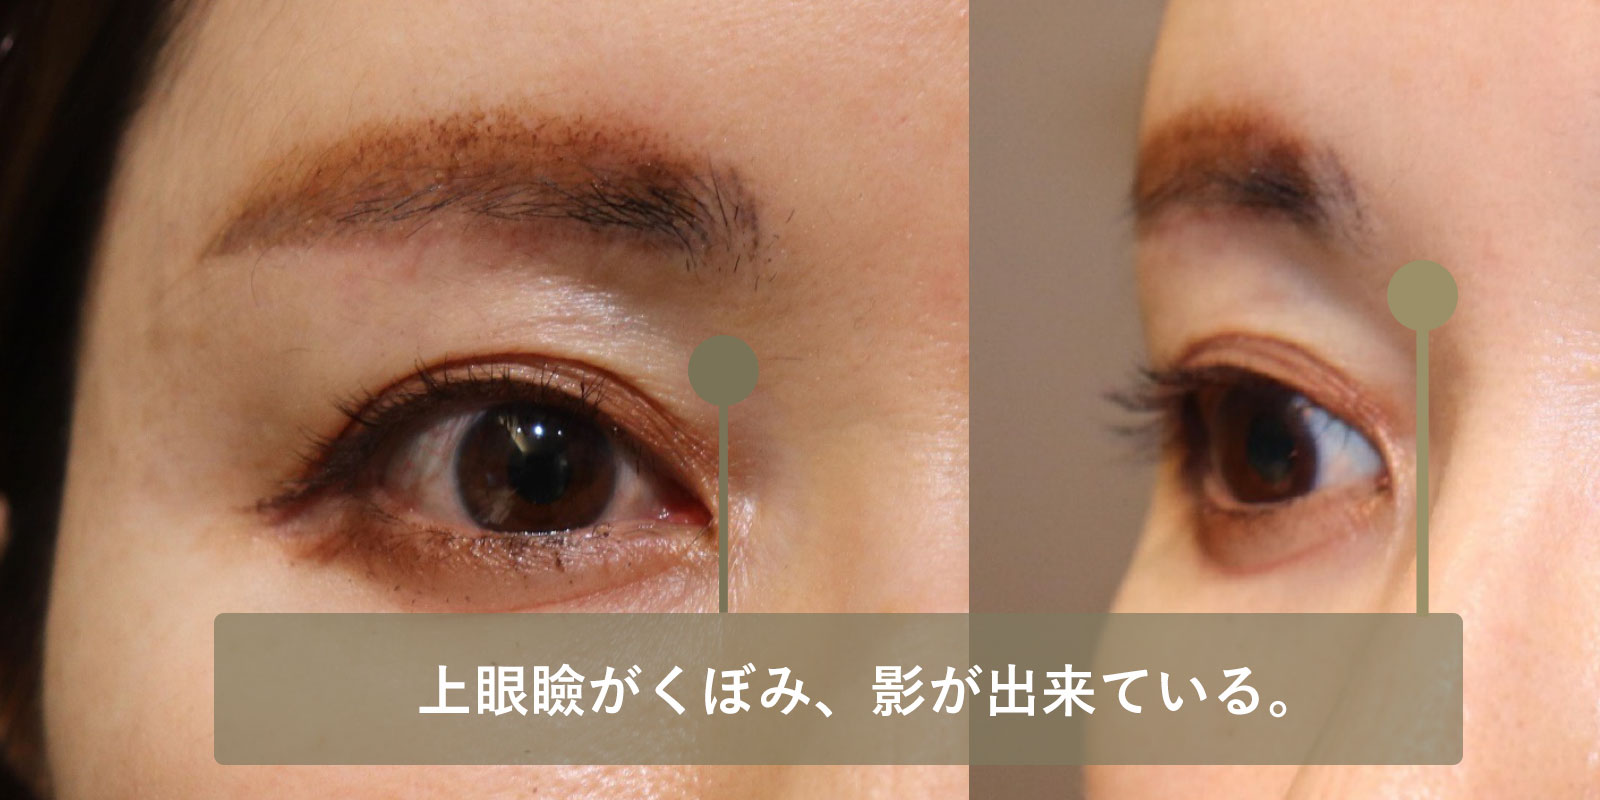

| 術前 | 上眼瞼がくぼみ、影が出来て眉毛の位置よりも眼球が後ろにあることが分かる。 |

|---|---|

| 術後 | 眼球が突出して影が消失し、眉毛の位置と眼球の位置がほぼ同じになっている。 |